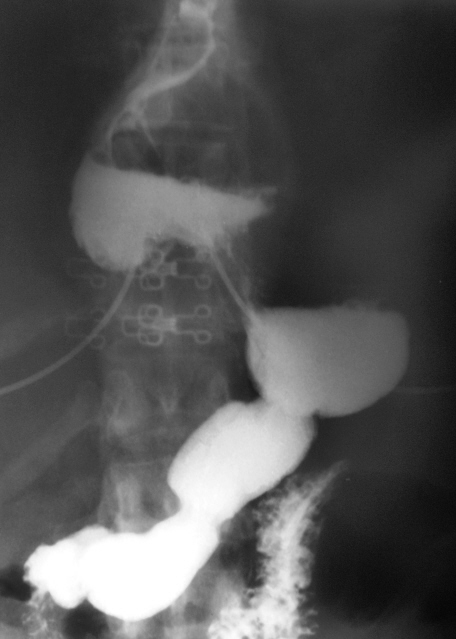

В процессе рентгенологического исследования ЖКТр

Приложения:

p8070117.jpgp8070118a.jpgp8070119a.jpgp8070123a.jpgp8070125a.jpg

ГПОД.